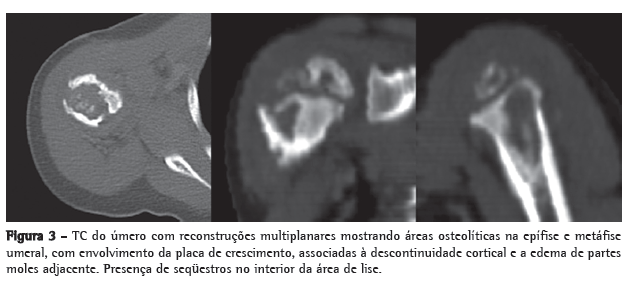

Menino de 21 meses, nascido em São Paulo, foi atendido com febre e leve comprometimento funcional do membro superior direito. A criança apresentava episódios de febre diária (acima de 38°C), predominantemente noturna. Uma semana antes da consulta, tinha iniciado com dor à palpação e à movimentação, bem como limitação de movimento do braço direito. A mãe negava história de trauma local. A radiografia do membro superior direito mostrou lesões osteolíticas na epífise e metáfise proximais umerais com bordas mal definidas, circundadas por áreas de esclerose óssea reativa, reação periosteal e aumento de partes moles (Figura 1). A ressonância magnética mostrou áreas de sinal medular anormal e edema de tecidos moles com realce pelo meio de contraste da medula infectada, sinais compatíveis com osteomielite no úmero proximal (Figura 2). O paciente recebeu cefalosporina por 10 dias em regime ambulatorial. No oitavo dia de antibioticoterapia, a criança veio a nosso serviço em virtude da febre e dor persistente.

A radiografia mostra lesões líticas com halo esclerótico, reação periosteal e osteoporose periarticular.(4,9-11) O estudo histopatológico mostra inflamação granulomatosa com células epitelioides, com ou sem necrose caseosa. Bacilos álcool-ácido resistentes são detectados em cerca de metade dos casos, e a maioria apresenta reação forte para PPD.(9,12)

Lesões líticas e escleróticas ósseas com reação periosteal caracterizam as lesões radiográficas. Os achados de TC na epífise, na metáfise e na diáfise foram consistentes com a descrição prévia em pacientes jovens.